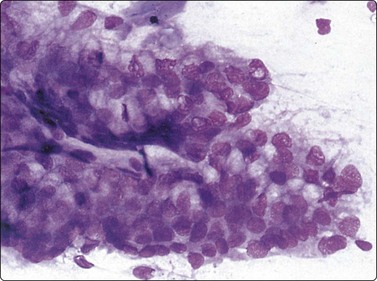

Benign prostatic hyperplasia (BPH) (Fig. 13.2)4,5,34,36,37,39

image

Fig. 13.2 Prostate, benign hyperplasia

Honeycomb-like sheets of uniform glandular epithelial cells; note visible cell borders and coarse cytoplasmic granules in A (A, DQ; B, Pap, HP).

Cohesive monolayered sheets of glandular epithelial cells can be quite large with distinct boundaries; most cells are seen on end and appear polygonal with centrally placed nuclei. The abundant pale cytoplasm and the distinct cell membranes give the sheet a honeycomb appearance (Fig. 13.2A,B). Only at the periphery are some cells seen in profile as columnar.

The main criteria of benignity are the uniform distribution of nuclei within monolayered sheets, distinct cell membranes, low N : C ratio and intracytoplasmic secretory granules (Fig. 13.2A). The granules stain dark magenta with DQ but are less conspicuous in alcohol-fixed Pap-stained smears. Although granules are not present in all benign epithelial cells, they are rarely present in carcinoma cells and absent in epithelial cells from rectal mucosa.